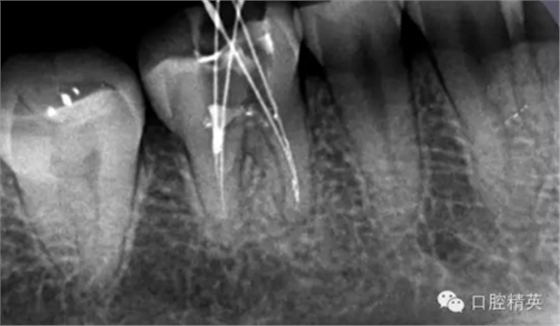

這個(gè)也是我目前接到最有難度的器械分離病例,從片子上看近中器械分離兩節(jié),曾在外院做過干尸,有七年。當(dāng)看到這個(gè)病例時(shí)我沒有多大的把握,因?yàn)槲沂巧硖幓鶎?,無(wú)顯微,無(wú)放大。我只有抱著試一試的態(tài)度,但是她是我們?cè)簝?nèi)員工,壓力很大。

現(xiàn)在開始看第二張片子我疏通的遠(yuǎn)舌根,有點(diǎn)問題哦!~

根尖孔偏移,或者是片子角度問題,導(dǎo)致我們很難判斷,感覺像是測(cè)穿。但是我們有根測(cè)儀(前提它是好的),因?yàn)楦鶞y(cè)儀是我們目前對(duì)根管測(cè)量最具有說(shuō)服力,也是最為客觀事實(shí)的。根測(cè)儀沒有顯示一探入根尖下三分之一顯示“over”的情況(我用的是登士博根測(cè)儀)根管內(nèi)無(wú)滲出,可以測(cè)出根管的長(zhǎng)度。那就證明工作長(zhǎng)度的存在,和可信。在看看正題的近中根的器械,我想問問大家覺得是什么器械??

近中舌根疏通,兩根分離的器械都在近中舌根?;ㄙM(fèi)2個(gè)多小時(shí)。將它疏通下去還是離不開較長(zhǎng)的時(shí)間,也就是耐心,它真的很重要哦!~第二個(gè)我覺得器械分離的疏通,就是在于能否建立旁路,那么怎么去建立這條路。我個(gè)人覺得首先挫的選擇,是k挫,是c+,還是別的什么。我的首選是8號(hào)c+,因?yàn)樗鼔蛴玻?號(hào)的k挫太軟,沒有辦法擴(kuò)下去,很容易碰到根內(nèi)部器械導(dǎo)致器械報(bào)廢,尖端變光亮。但是c+挫也不是那么完美,我擴(kuò)的時(shí)候用了4根8號(hào)新的c+挫,全部報(bào)廢。尖端彎曲90度的,有變成麻花的。這些都在提醒我可能用力過大,或者根管內(nèi)部太過于復(fù)雜。疏通時(shí)只有慢慢來(lái),一點(diǎn)點(diǎn)的下千萬(wàn)不要妄想一步到位。手法還是要輕柔否則你的器械一樣也會(huì)分離進(jìn)去。疏通到挎自己的器械的時(shí)候也是碰到分離的器械時(shí),這個(gè)時(shí)候最好是上下提拉,切勿旋轉(zhuǎn)向下,你只有盡量將該部位擴(kuò)開,為下一步往下疏通留有足夠的空間就好。而不是繼續(xù)向下旋轉(zhuǎn),這樣會(huì)導(dǎo)致器械的分離,加大你疏通的難度。

近中試尖,超出,這是沒有很好的把握工作長(zhǎng)度,這是自己在預(yù)備時(shí)可能出現(xiàn)超預(yù)備的情況,所以以后機(jī)括預(yù)備一定要注意,防止超預(yù)備,否則會(huì)導(dǎo)致術(shù)后疼痛。